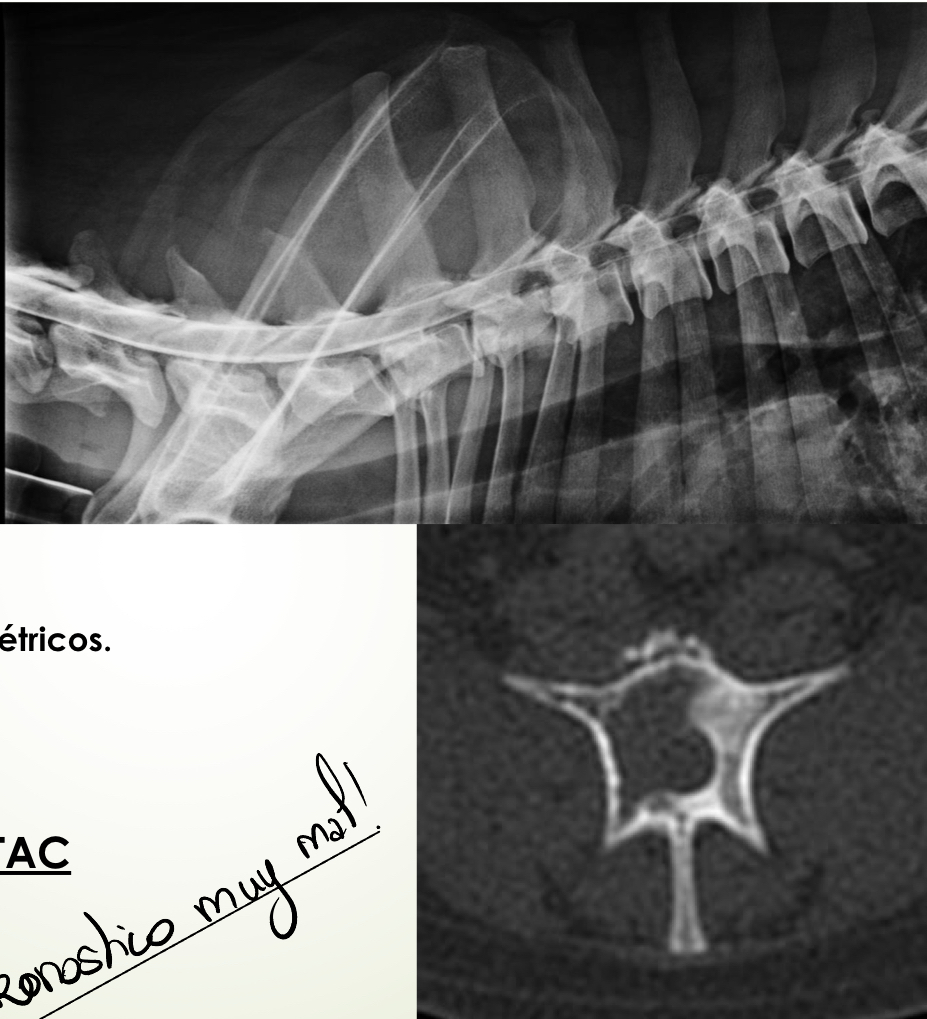

Neoplasia

A

Extradural :

* Vertebrales o no

* Dolorosos

Intramedular :

* No dolorosos

SC : suelen ser progresivos y asimétricos

Dx : Rx mielografía, RM, TAC

Pronostico muy mal!!